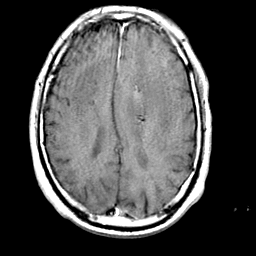

Meningioma, MR Study #1 -- Slice #13

[Home][Help][Clinical] Slice 13